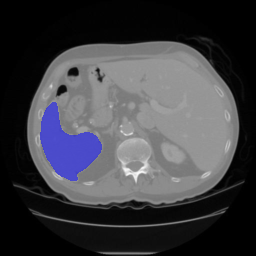

The qualitative results for the proposed and competing methods are shown in Fig. 3. The quantitative results comparison of the proposed method to the four state-of-the-art methods are shown in Table 1. The results reveal that the proposed method comfortably outperform other studied methods for smaller fractions of annotated data (e.g. Spleen 5%). The gap between the Duo-SegNet and other competitors decreases on the Nuclei dataset, when the amount of labeled data increases. That said, we can still observe a significant improvement on the Heart and Spleen dataset. The proposed network can produce both accurate prediction masks and confidence maps representing which regions of the prediction distribution are close to the ground truth label distribution. This is useful when training unlabeled data. Fig. 2 shows the visual analysis of confidence maps.

| Input | GT | Prediction | Confidence Map |

Spleen |

![]() |

| Input | GT | Fully Supervised | Mean Teacher | Pseudo Labelling | VAT | Deep Co-training | Duo-SegNet (Ours) |